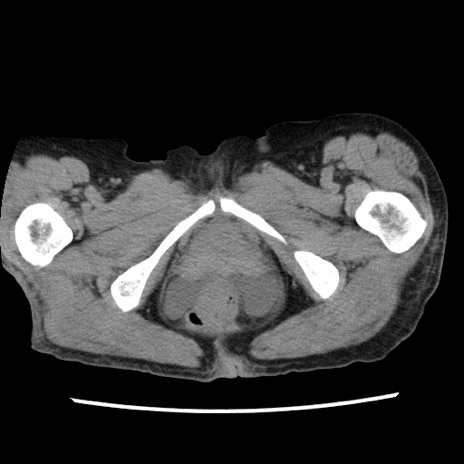

症例1(横断像)

【症例】80歳代女性

【主訴】腹痛

【現病歴】8時間前から腹痛あり来院。

【既往歴】糖尿病、脂質異常症、子宮体癌にて子宮全摘術

【身体所見】意識清明・会話良好だが腹痛で苦悶様、全腹部にわたって反跳痛と圧痛あり

【データ】WBC 13600、CRP 0.14、LDH 224、CK 90